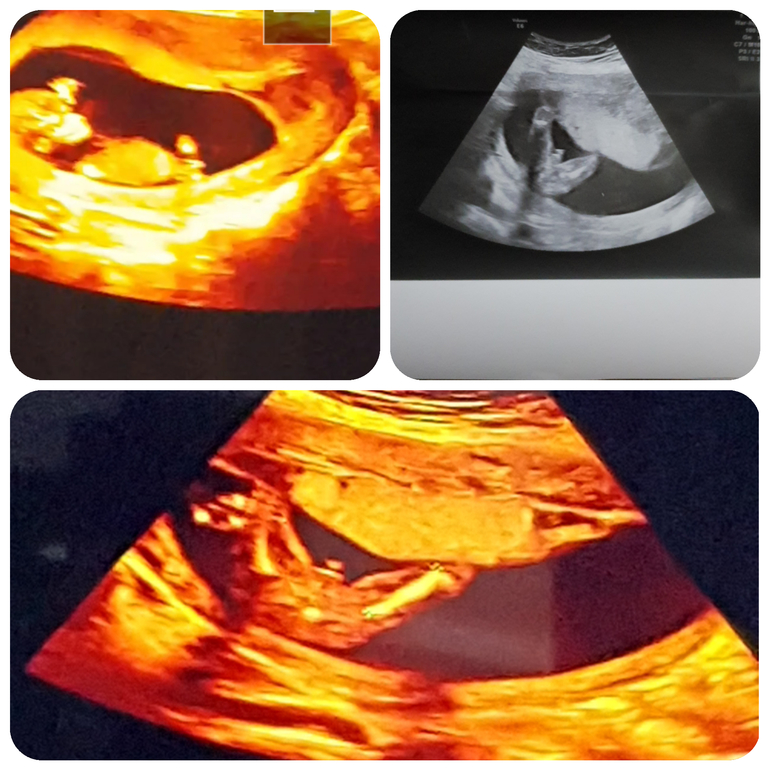

Уррррррррраааааа!!!!Мой нежданчик девочка стал внезапно МАЛЬЧИКОМ!!!

Результаты: УЗИ, КТГ, доплера, скринингаУзи вчера,,проплакала весь вечер,,от радости,,ребенок шевелится сердечко стучит все хорошо а самое главное что чудо и приходится перекрашивать кружочек в синий цвет ,,,и у нас будет СЫН,,

такой долгожданный,,17 лет я жду его и вот наконецто,,после 3 узи и предположений врачей девочки ,,,да и на форумах всем казалась девчачья пипирка,,,а в итоге все кроме метода Рамзи ошибался,,

Вот это новость! Поздравляю! Тут сомнений быть не может. На ранних фотках казалось, что девочка из-за плохого качества.